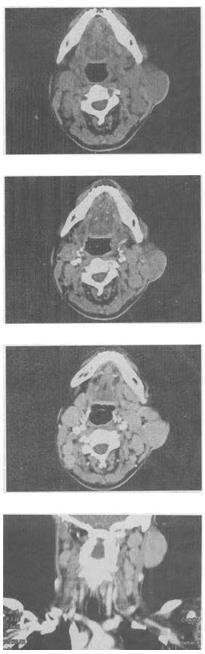

- 单项选择题 女,25岁,发现双侧颈部肿块近10年,CT如图,最可能的诊断为()。

A、巨淋巴结增生症

B、淋巴瘤

C、转移瘤

D、淋巴结结核

E、淋巴结炎

- A